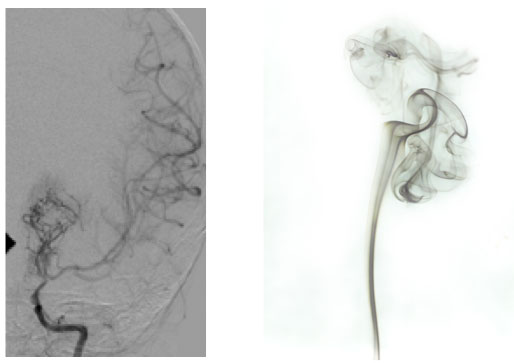

Questo quadro (poi confermato anche dall�angiografia) (Figura 3) � diagnostico di malattia di Moyamoya.

Figura 3. Caratteristico aspetto angiografico.